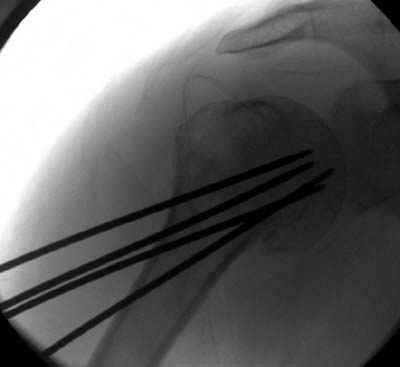

Пока я пользуюсь методикой принятой у нас (методика Сиэтла), также перкутанный спицевой метод, только сцицы 2.8 мм с резбой на конце.

Здесь случай перелома-вывиха плеча, больному 56 лет, после "дважды" закрытой неудачной репозиции, опять же ургентно взяли в операционную, после полного общего обезболивания попытались сделать репозицию, и фиксацию провели спицами.

Больной находился в повязке, примерно напоминяющей косыночную, рекомендованы движения в локтевом суставе и маятниковые движения в плече, спицы удалены в три недели (были случаи миграции)